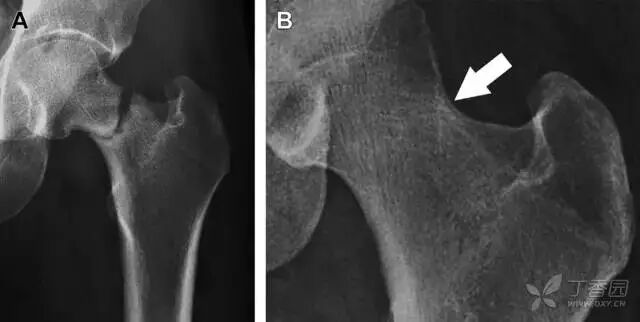

01髋臼骨折

髋臼骨折最常见的类型是髋臼后壁骨折,几乎占髋关节骨折的 1/4,且常常合并髋关节后脱位。由于骨性结构重叠,可能肉眼看上去觉得非常轻微的骨折,事实却并非如此。髋臼后缘中断常常是髋臼后壁骨折的一个特征(图 2)。

图 2 为髋臼后壁骨折伴髋关节脱位患者。A 右侧髋关节 X 线片示股骨头后方可见一骨折线(箭头),髋臼后缘中断。B 左侧髋关节 X 片对照可见髋臼后缘连续(箭头)。C  CT 三维重建图像示髋臼后壁缺损,可见旋转、移位的骨折块(箭头)